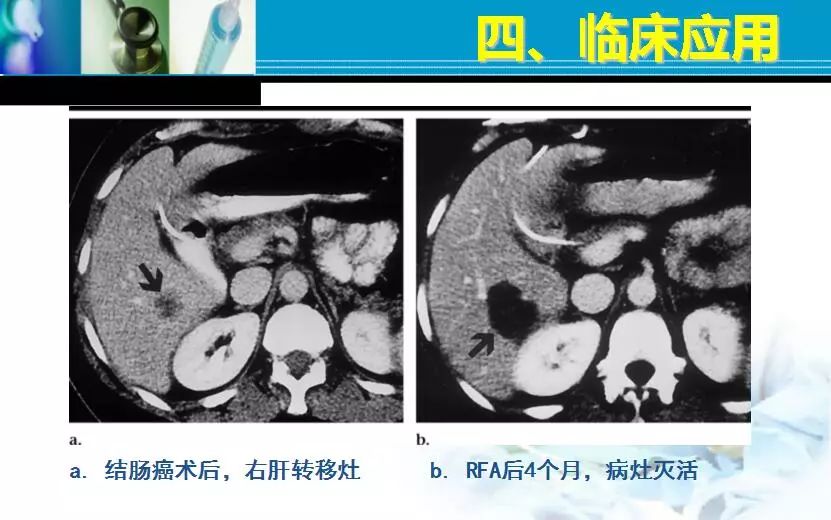

胃癌、贲门癌、乳腺癌、直结肠癌肝转移

TACE,HAL,HAE,DDS,PEI,微波,射频。